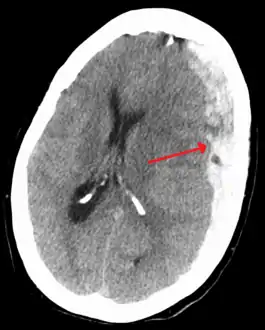

![]() ورم دموي تحت الجافية مُشار إليه بالسهم الأسود، ويتميز بتغير كبير في مكان خط الوسط. ورم دموي تحت الجافية مُشار إليه بالسهم الأسود، ويتميز بتغير كبير في مكان خط الوسط. | |